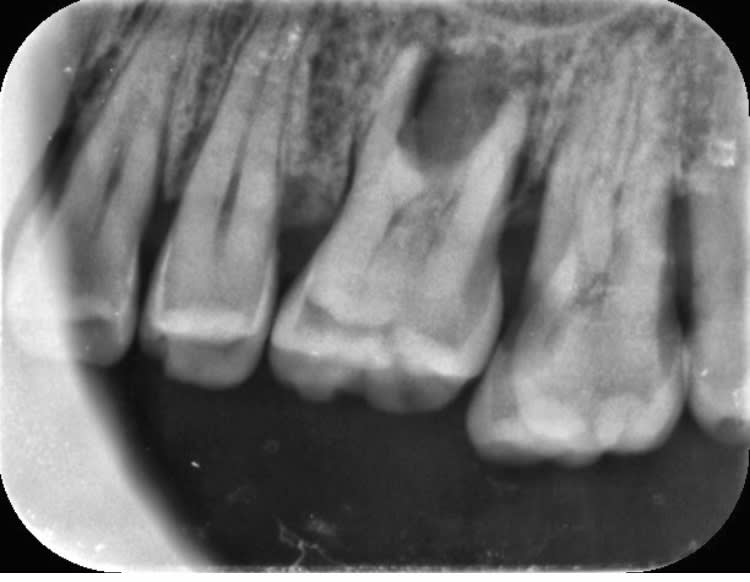

Bon à mon tour... infection à répétition sur cette 37 support de bridge.

Alvéo mésiale distale, curetage et remis la dent avec un cavit. Je croise les doigts!!